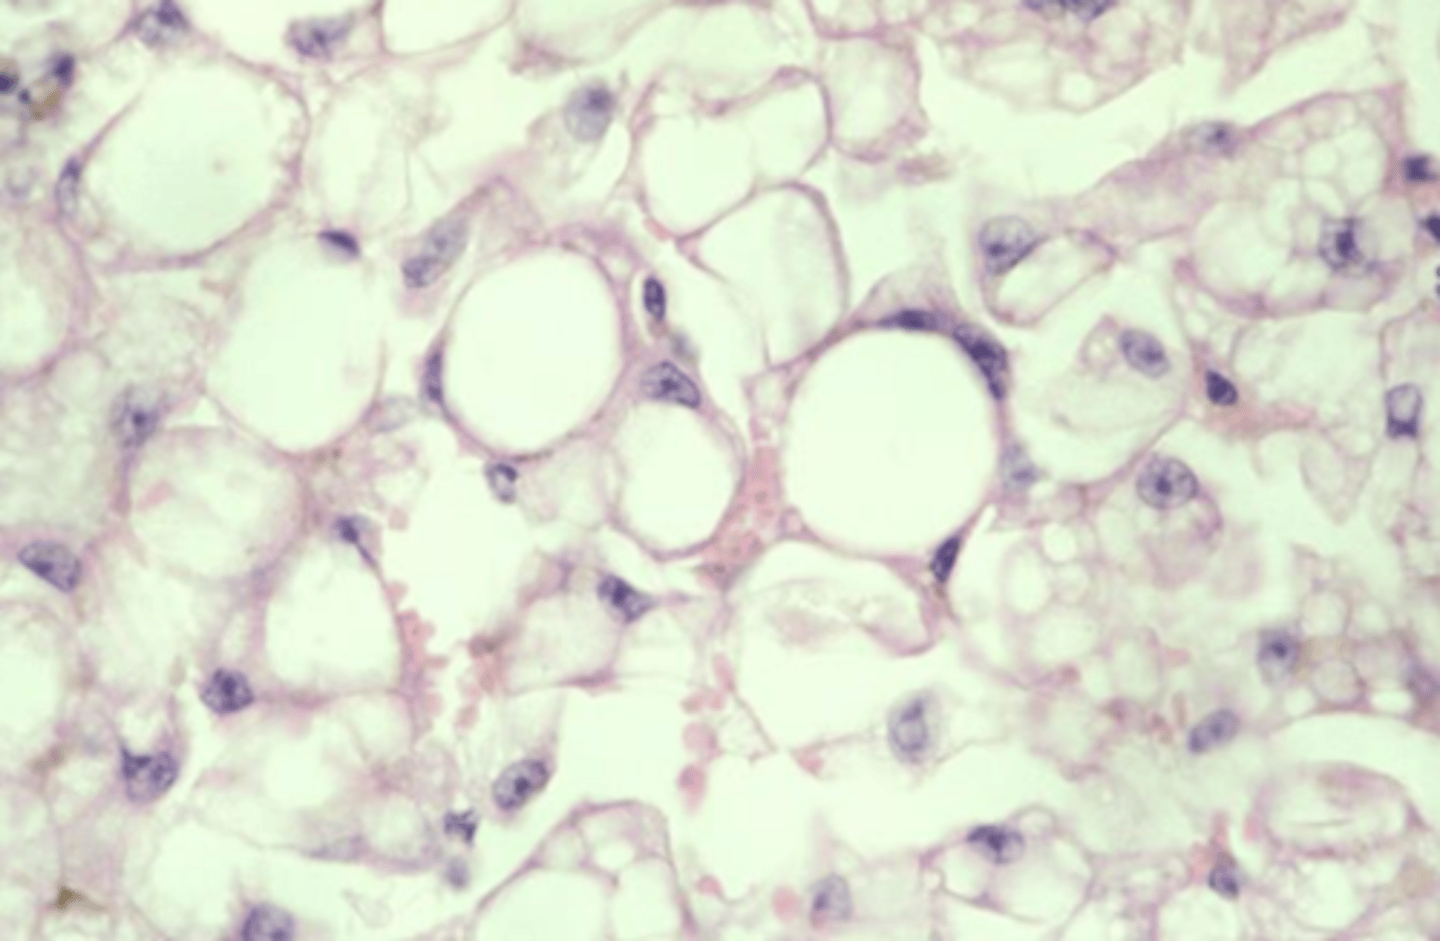

macrovesicular hepatic lipidosis

yellow arrow?

microvesicular hepatic lipidosis

blue arrow?

displaced nucleus

blue arrow

macrocytic lipidosis - large cytoplasmic vacuole

yellow circle?